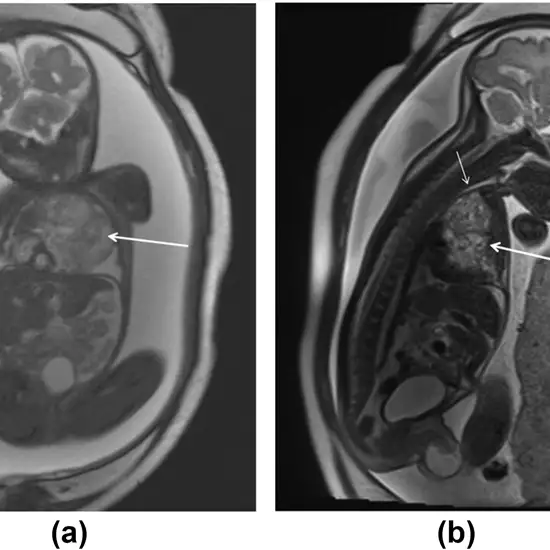

A fetal MRI is known to be a noninvasive imaging test which offers a more detailed and clear information about the anatomic structures of the fetus, thus, providing high-resolution images.

It is usually performed in the 2nd or 3rd trimester of the pregnancy. This type of examination is used to evaluate abnormalities in the baby's brain, spine, and body.

The MRI may also be used to confirm an ultrasound diagnosis or add significant diagnostic information in complex cases.